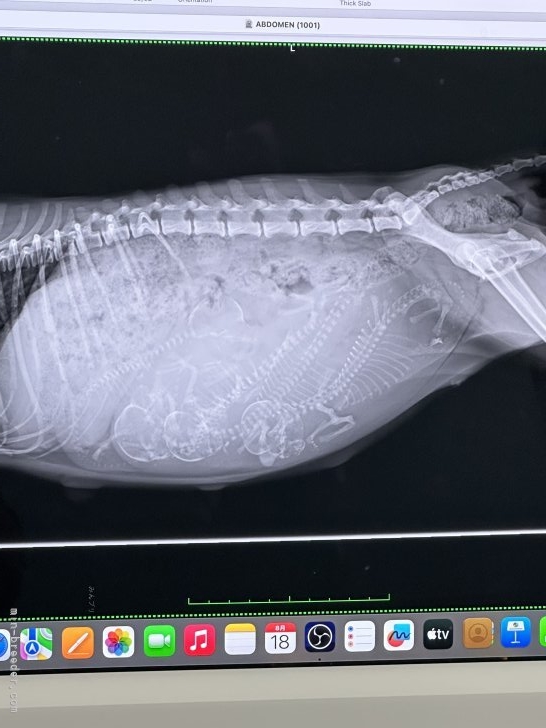

自然のことなので、獣医さんにエコー

みてもらっても、いざ

最終のレントゲンとなると

増えてたり、減っていたり。

なので産まれるまでの

お楽しみにします。